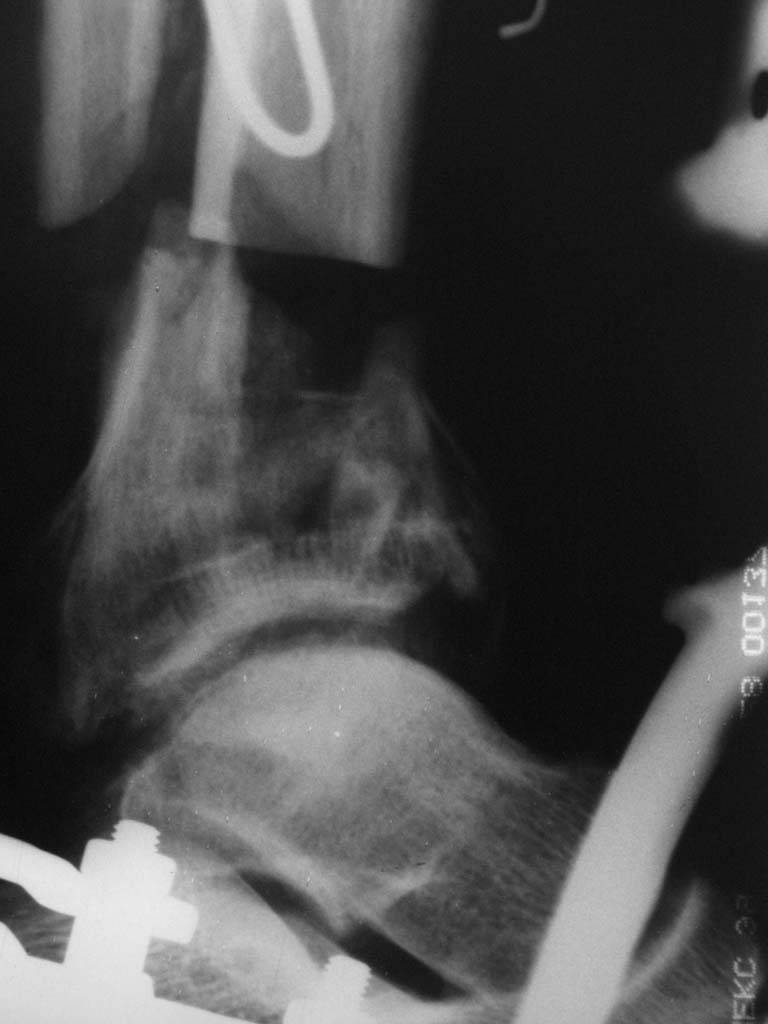

В случае гладкого заживления раны, при условии положительного решения вопроса с металлом, планируем перемонтаж аппарата Илизарова, дополнительную резекцию дистального отломка, выведение полокости голеностопного сустава в правильное положение (см. боковую Р-грамму), одномоментно остеотомия большеберцовой кости. После восстановления длинны голени, по всей видимости, артродез голеностопного сустава.

Рентгенограммы прилагаются. Фото местного статуса выложу в ближайшее время.

Мы обычно не фиксируем малоберцовую кость. Просто стараемся сопоставить ее концы за счет хорошей репозиции. В представленном случае имеется некоторое смещение дистальных фрагментов кнаружи, и, как мне кажется, ротация их вместе со стопой кнутри (ротация хорошо заметна на прямом снимке по форме таранной кости и на боковом по соотношению отломков малоберцовой). Если это действительно так, то это несложно сейчас постепенно устранить в аппарате. И тогда концы малоберцовой кости будут находиться поближе друг к другу.